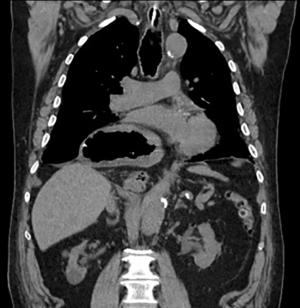

The first and most important step in patients with incarcerated GHH is to decompress the stomach. Incarcerated GHH are often difficult or impossible to decompress with a nasogastric tube placed at bedside due to gastric angulation within the chest. A bedside nasogastric tube will either not pass the GEJ or will only decompress a portion of the stomach, while the remainder of the stomach is still dilated (Figure 1). In our experience, endoscopic decompression with fluoroscopic guidance under general anesthesia is the safest and most effective management of an incarcerated GHH.